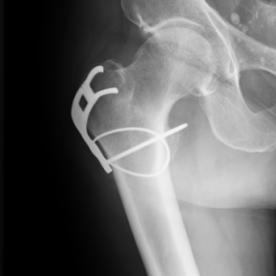

Röntgenbilder